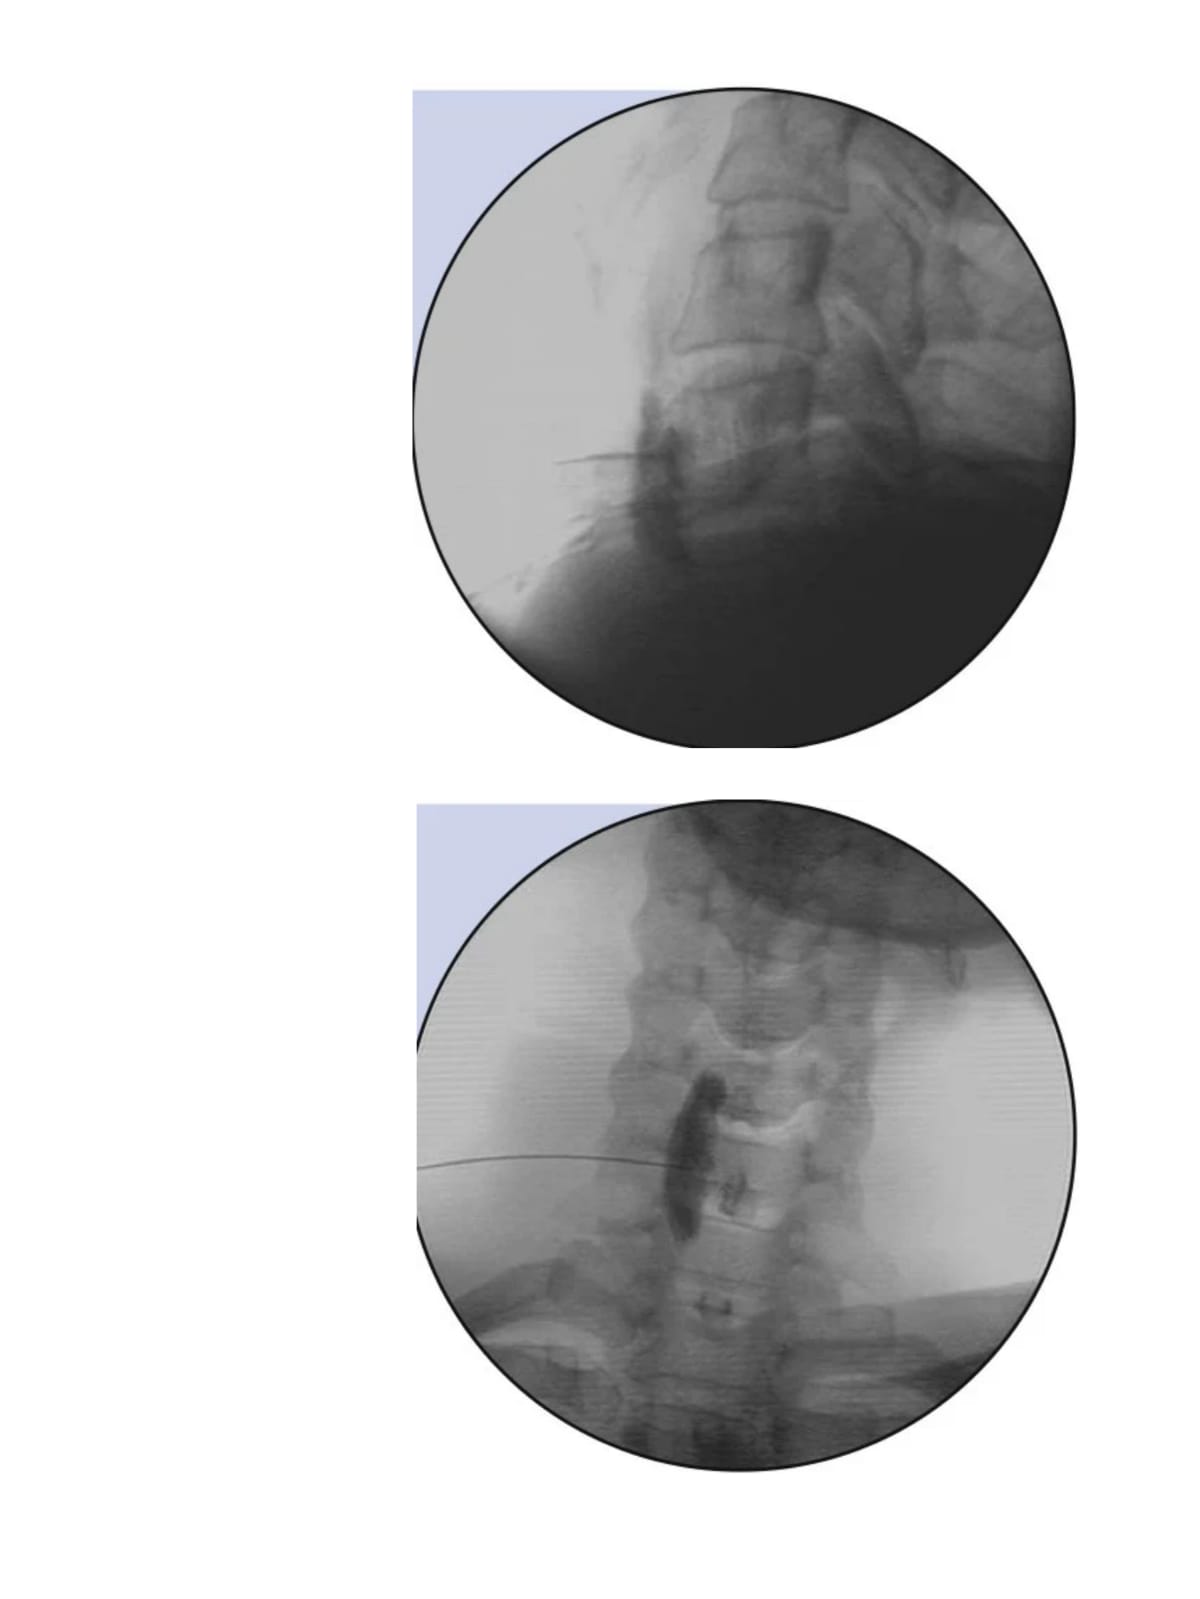

About Imaging Guided Procedures

This involves the use of imaging to target painful structures for injection of regenerative therapy (Biologics) and identify nerves carrying painful sensation and target them to achieve pain relief.

Different types of imaging used in pain practise are fluoroscopic guidance and Ultrasound guidance.

Spine

- Transforaminal epidural

- Ganglion impar injection

- Intra articular facet joint injection

- Caudal neuroplasty

Miscellaneous

- Stellate ganglion block

- Lumbar sympathectomy

- Nerve block injections